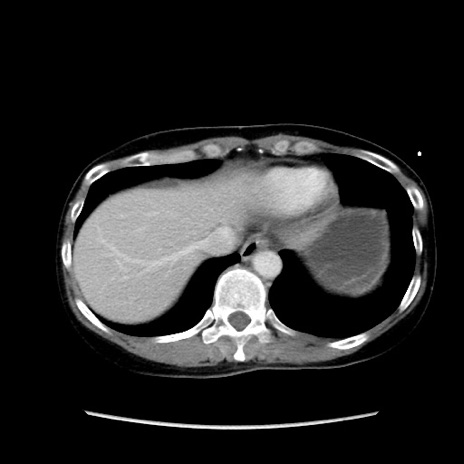

症例32(横断像)

【症例】40歳代 女性

【主訴】上腹部痛、嘔気・嘔吐

【現病歴】約9時間前頃から急に上腹部痛、嘔気、嘔吐が出現。改善しないため救急要請。

【既往歴】子宮頚癌(広汎子宮全摘術、放射線療法)、腸閉塞

【身体所見】腹部:平坦、軟、腸雑音亢進、上腹部を中心に腹部全体に圧痛あり。

【データ】WBC 8400、CRP 0.03